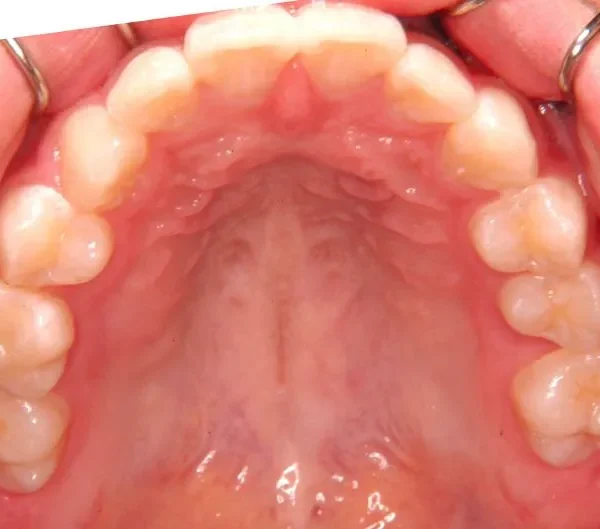

初診時

初診時年齢 小学校6年生 (女性) 主訴 犬歯がずれている・噛み合わない

診断名 叢生・交叉咬合 装置名

右下の犬歯がずれて生え噛み合わせの邪魔をしています。